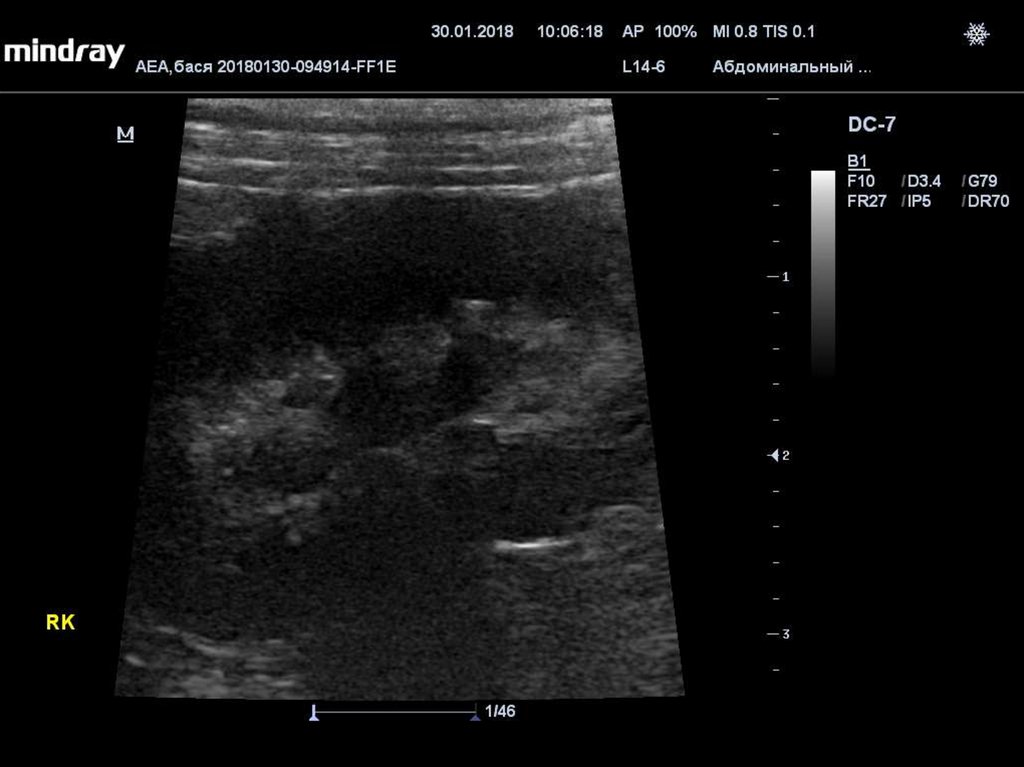

Неоплазия

• Многие опухоли продуцируют ПрПТГ и другие

компоненты, приводящие к гиперкальциемии (IL, TNFα,

TGF-a, кальцитриол).

• Метастазы в костную ткань могут усиливать резорбцию

костей.

• Распространенность гиперкальциемии при лимфоме у

собак 20%-40% (1), у кошек 30%-35% (2).

• Т-клеточная лимфома - наиболее распространенная

причина гиперкальциемии у собак (3)